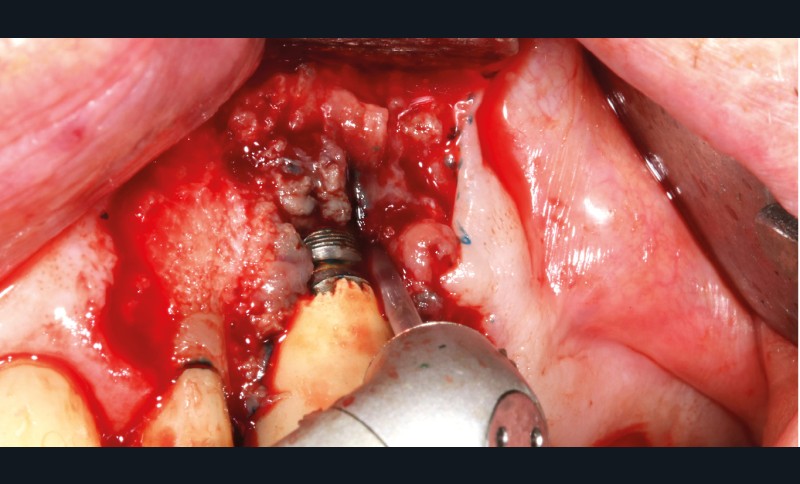

– Le laser Er-YAG, utilisé pour le nettoyage, est un laser avec un milieu actif composé d’yttrium, d’aluminium et de grenat dopé à l’erbium. Avec une longueur d’onde de 2 940 nm situé dans l’infrarouge, le laser Er-YAG est un laser à haute énergie, dont la lumière est absorbée dans l’eau et dans l’hydroxyapatite et qui ne pénètre pas profondément. Ceci permet de couper des tissus mous et des tissus durs, mais également de désorganiser le biofilm bactérie.

C’est un laser idéal pour le traitement chirurgical des péri-implantites. Il permet l’élimination du tissu de granulation à la surface de l’implant et de l’os ainsi qu’une décontamination mécanique par effet photoablatif.– Le laser Diode, utilisé pour la décontamination…